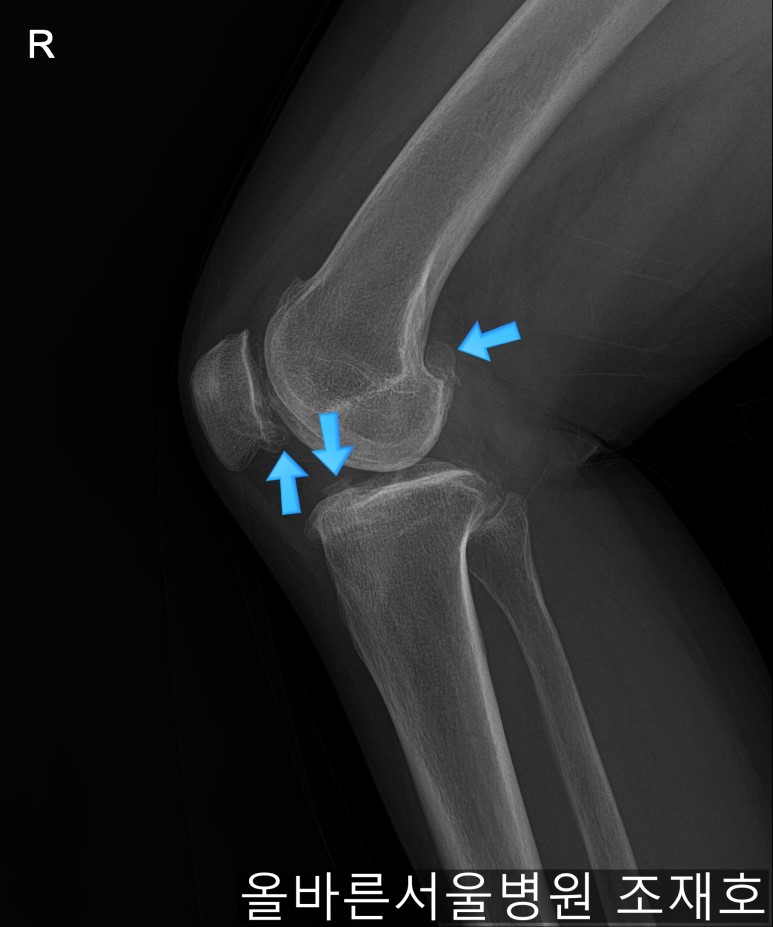

仅通过放射线片子观察到:右膝由于炎症严重,内侧胫骨及股骨已接触在一起,向内测严重变形。

左膝虽然也观察到了炎症,但远不如右膝严重。

如果通过X光片也观察到相同的病症,可以判断内侧关节的软骨大部分都损伤了。

通过观察侧位片子可看到:由于关节炎已经长出骨刺。髌骨关节有炎症。

虽然有髌骨关节炎,但软骨损伤不算严重。